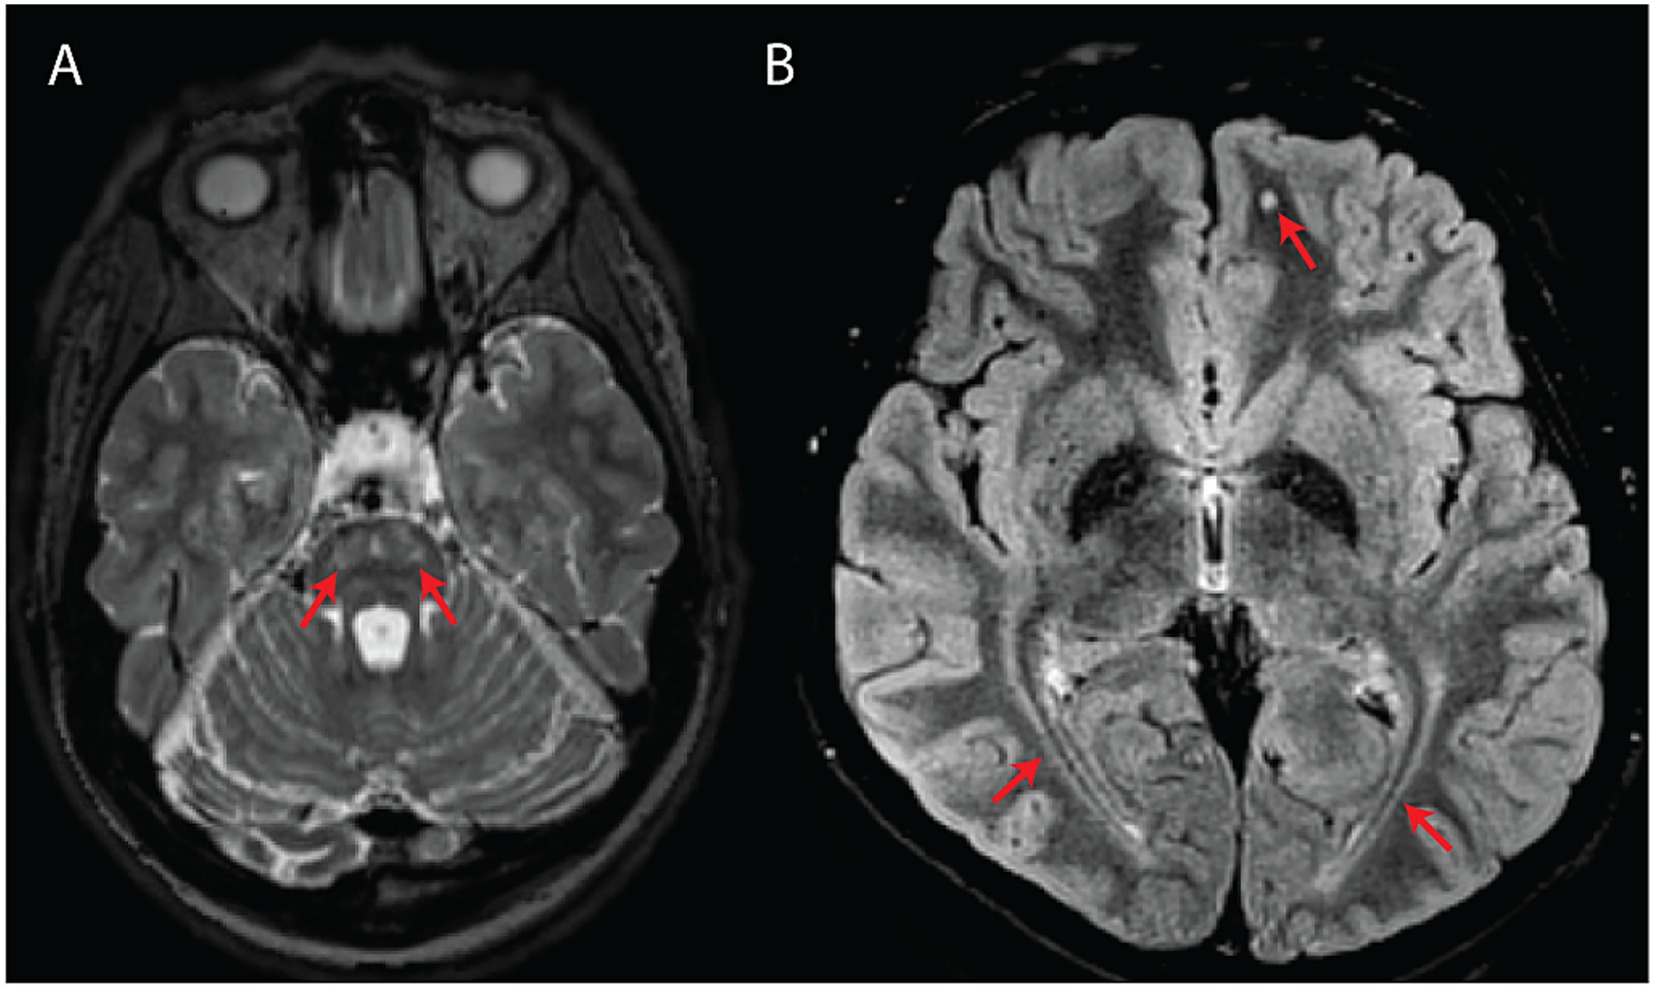

The mean age at the latest MRI available for review was 29 years old (range = 14–60 years). All subjects demonstrated at least one neuroradiological feature typical of WFS (Figure 1) (12–15). For 11 subjects (n = 11/17; 65%), two timepoints were available for assessment (mean follow-up MRI duration = 5.3 years).

Figure 1

Classical MRI features associated with WFS. (A) Axial T2-weighted image showing bilateral pontine signal abnormality (subject #10). (B) Axial T2-FLAIR image showing bilateral symmetric posterior white matter abnormal signal as well as a punctate, round white matter signal abnormality in the left frontal lobe (subject #14).

3.3.1 Classical WFS-associated features

Involvement of the posterior periventricular white matter and/or optic radiations was the most common finding (n = 15/17; 88%), followed by punctate subcortical white matter changes (n = 9/17; 53%), pontine signal changes (n = 7/17; 41%), brainstem atrophy (n = 6/17; 35%), cerebellar atrophy (n = 5/17; 29%), diffuse/confluent involvement of the centrum semiovale and/or peritrigonal white matter (n = 4/17; 24%), and absent/diminished T1-weighted posterior pituitary bright spot (n = 1/17; 6%).

Enlarged perivascular spaces (n = 3/17; 18%), corpus callosum abnormalities (n = 3/17; 18%), midbrain signal changes (n = 2/17; 12%), and abnormal occipital lobe gyrification with or without posterior horn ventricular enlargement (n = 2/17; 12%) were additionally observed.